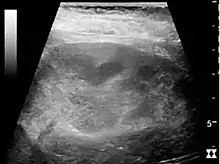

The kidney is divided into parenchyma and renal sinus. The renal sinus is hyperechoic and is composed of calyces, the renal pelvis, fat and the major intrarenal vessels. In the normal kidney, the urinary collecting system in the renal sinus is not visible, but it creates a heteroechoic appearance with the interposed fat and vessels. The parenchyma is more hypoechoic and homogenous and is divided into the outermost cortex and the innermost and slightly less echogenic medullary pyramids. Between the pyramids are the cortical infoldings, called columns of Bertin (Figure 1). In the pediatric patient, it is easier to differentiate the hypoechoic medullar pyramids from the more echogenic peripheral zone of the cortex in the parenchyma rim, as well as the columns of Bertin (Figure 2).[1]

Figure 1. Normal adult kidney. Measurement of kidney length on the US image is illustrated by ‘+’ and a dashed line. *Column of Bertin; ** pyramid; *** cortex; **** sinus.[1]